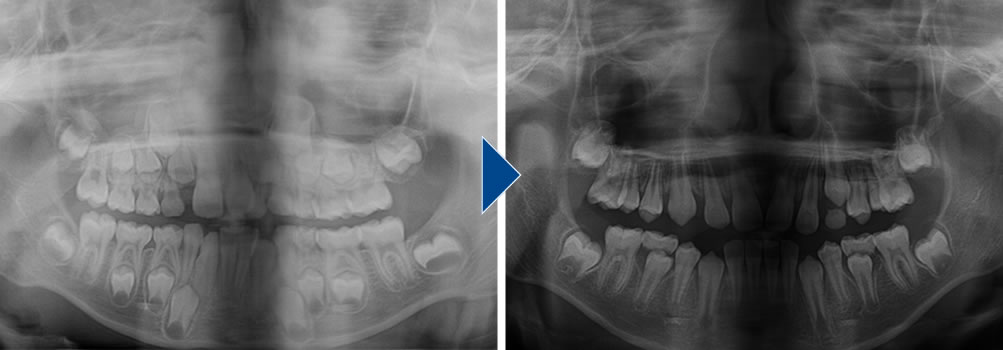

治療前後のレントゲン写真です。治療前の状態はスペースが不足していましたが、顎骨を拡大したことによって綺麗に歯を並べることができました。

治療前後のセファロレントゲン画像です。治療前に比べて僅かですが、上顎が前に出ています。早い段階で小児矯正を行うことで、負担を抑えて骨格の問題も改善することができます。